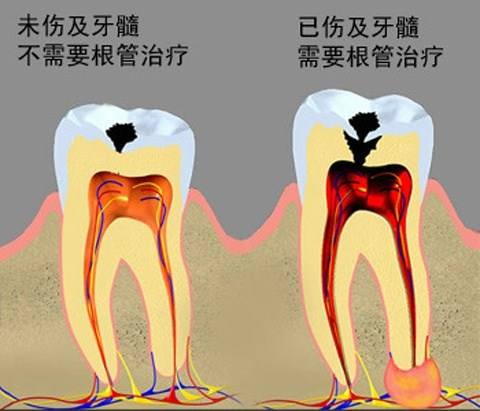

牙髓炎圖片

牙髓炎